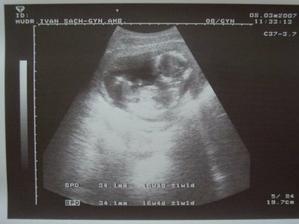

SRPŇÁTKA 2007 - fotky UTZ

album věnované mimískům, které se narodí v srpnu 2007 a jejich maminkám ze "Společného termínu SRPEN"